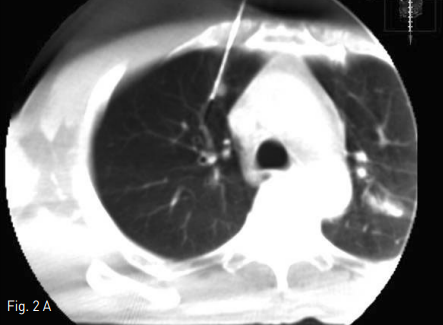

Fig 2B

Axial & sagittal cone beam CT (CBCT) scan show well targeted an electrode to the pulmonary nodule in RUL.

Fig 2A

Supine position에서 시행한 cone beam CT(CBCT)상 right lung의 upper lobe에 위치하는 약 7mm 지름의 결절은 관찰가능하였다. 통증조절을 위해 Lidocaine국소 마취와 Midazolam 2mg i.v. 하였다. CBCT guide 하에 2개의 2.5cm Octopus electrode(STARmed, Kyeonggi-do, Korea)를 병변에 삽입하였으며, 이중 upper electrode가 병변을 관통한 상태였고, lower electrode는 제거하였다(Fig.2). 12분간 RF ablation을 시행하였으며, CBCT상 병변 주변으로 ground glass opacty(GGO)가 형성된 것을 확인하였다 (Fig. 3). 마지막 CBCT상 RF ablation 으로 인한 volume loss로 인하여 mediastinal pleura 가 병변쪽으로 deviation된 것이 관찰되었고, 출혈, 기흉 등의 합병증은 없었다. 시술 중 통증은 경미하였다.